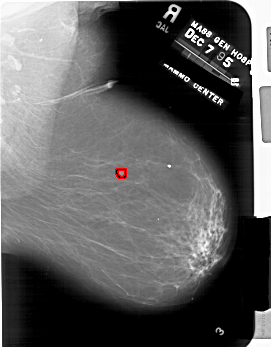

A_1863_1.LEFT_MLO

LEFT_MLO LINES 6871 PIXELS_PER_LINE 4981 BITS_PER_PIXEL 12 RESOLUTION 43.5 NON_OVERLAY

FILE: A_1863_1.RIGHT_MLO.OVERLAY

TOTAL_ABNORMALITIES 1

ABNORMALITY 1

LESION_TYPE MASS SHAPE IRREGULAR MARGINS MICROLOBULATED

ASSESSMENT 4

SUBTLETY 4

PATHOLOGY BENIGN

TOTAL_OUTLINES 1

BOUNDARY